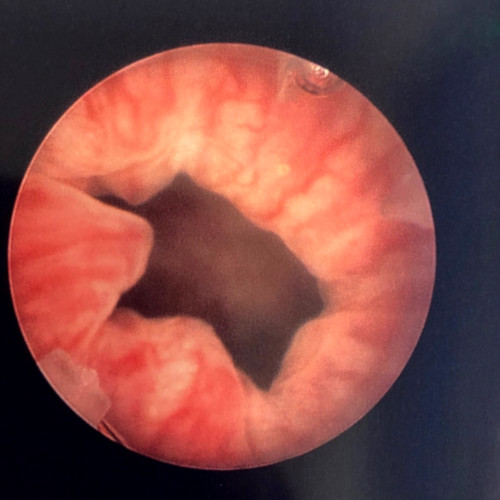

Femme de 65 ans, échec de bandelette sous urétrale trans-obturatrice. Pas de prolapsus génital. Fuites en jets à la toux. Pression de clôture urétrale abaissée à 25 cmH2O, Valsalva leak Point positif avec des poussées de 30 cm H2O. Probable insuffisance sphinctérienne intrinsèque. Avant et pendant l’injection, on observe le bombement de la muqueuse sous l’effet du comblement. Le geste n’est pas très compliqué mais nécessite quand même un peu de dextérité et comme d’habitude, l’expérience améliore les résultats.